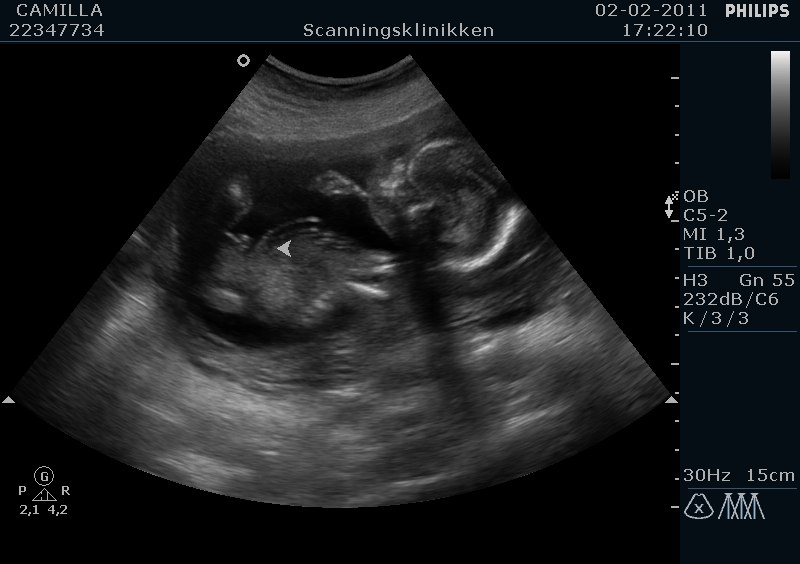

Hej alle sammen. Flertallet fik ret: Vi skal have en skøn lille dreng :-D :-D

Fik sgu tårer i øjnene da jeg fik øje på tappen! Så stort!

I får lige nogle billeder :-)

Tillykke med ham, hvor er det bare dejligt og hvor er han lille og fin på scanningsbillederne...

Ja er han ikke Vi fik hele 50 billeder på en cd rom, og så 5 stk i print